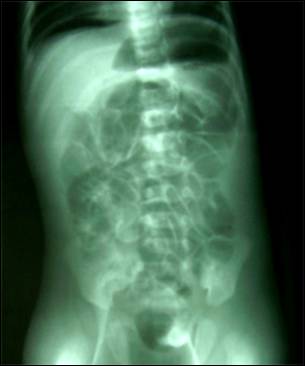

Image 2: X-ray

Abdomen (erect) showing free gas in the peritoneum (under the right dome of

diaphragm) and free gas in the scrotum.